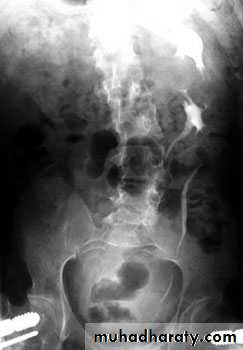

Bulb of follys cathter IVU with bilateral mild to moderate degree of HN

RT sided PUJ stenosis & obstruction with RT sided HN

Uretrocele (cobra head shape)distal both sided ureteric ends with dilated both ureters

Uretrocele